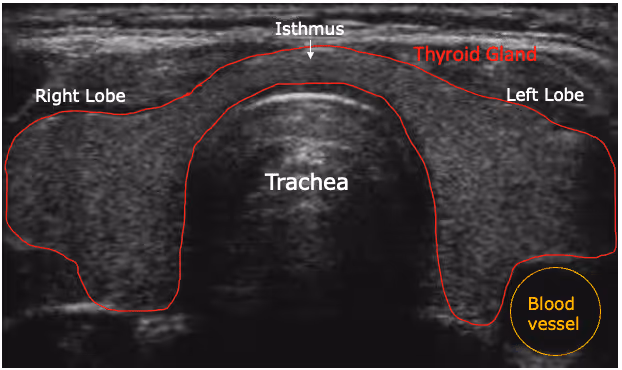

Thyroid ultrasound

Your doctor will recommend doing a thyroid ultrasound to assess the thyroid gland, which helps in knowing if it is functioning correctly. It is used to:

- Identify the size and shape of the thyroid gland

- Monitor the size of the thyroid gland during treatment

- Identify thyroid nodules and assess their size, shape, quantity, and whether they are benign or malignant

- Assess enlarged parathyroid glands, commonly linked to various conditions

- Assist in positioning a needle during a biopsy to collect a sample from a nodule for additional examination